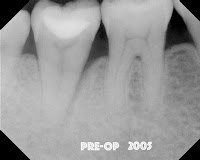

Four years later at another re-evaluation, the bone loss on the lateral is even worse. We are still puzzled at why this has not resolved, but not convinced there is a root fracture, so we decided to try intentional replantation. So, here are some of the best photos I have to document the process.